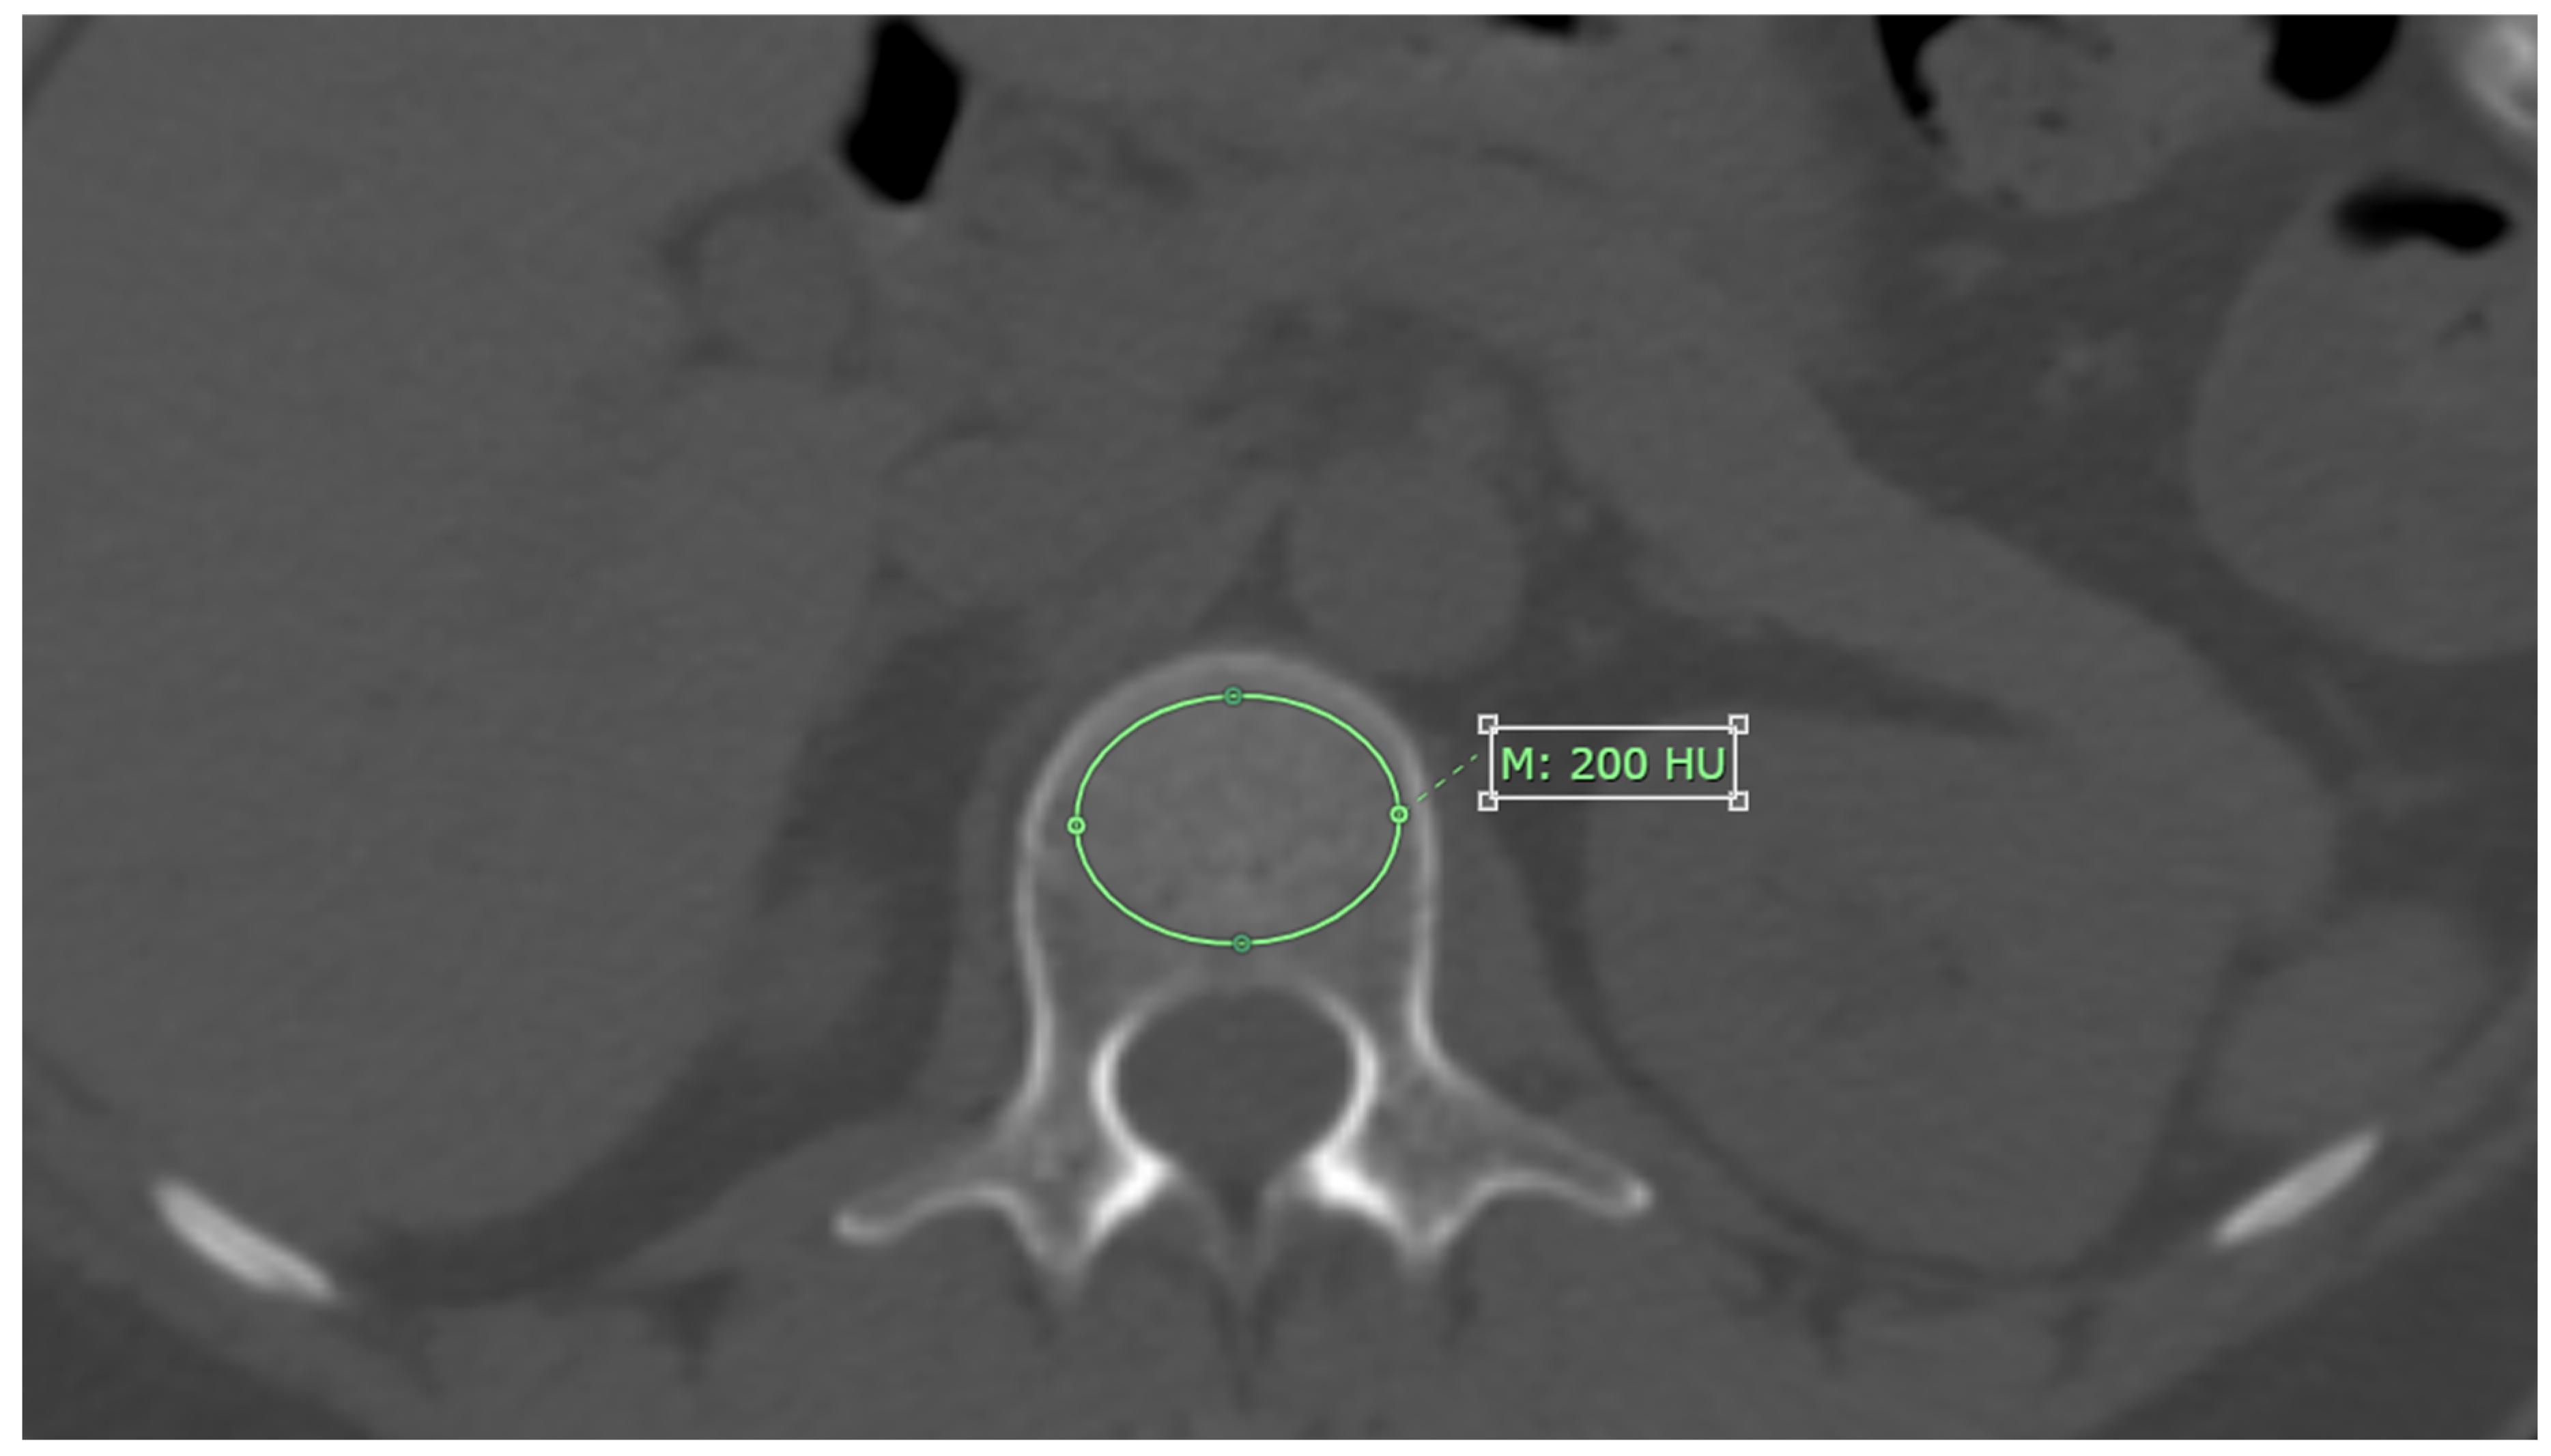

CT attenuation values for each L1-L4 vertebrae were measured on axial images from non-contrast CT scans, using bone window setting. The measurement was performed at the midpoint of each vertebra’s height, with the Region of Interest (ROI) placed specifically on the trabecular bone. The ROI was drawn as large as possible, avoiding areas with artifacts, degenerative changes, bone islands, or hemangioma, as shown in Figure 1. The results are reported in Hounsfield units (HU) [11].

Figure 1. The method for measuring CT attenuation values in cross-sectional images involves placing the region of interest (ROI) specifically on the trabecular bone area. In this approach, M represents the mean CT attenuation value.